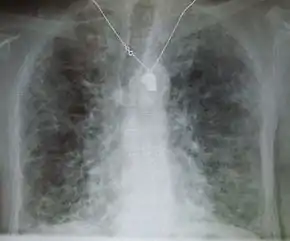

X-ray and CT (radiography and computed tomography)

Chest radiography is usually the first test to detect interstitial lung diseases, but the chest radiograph can be normal in up to 10% of patients, especially early in the disease process.[13][14]

High-resolution CT of the chest is the preferred modality and differs from routine CT of the chest. Conventional (regular) CT chest examines 7–10 mm slices obtained at 10 mm intervals; high resolution CT examines 1–1.5 mm slices at 10 mm intervals using a high-spatial-frequency reconstruction algorithm. The HRCT therefore provides approximately 10 times more resolution than the conventional CT chest, allowing the HRCT to elicit details that cannot otherwise be visualized.[13][15]

Radiologic appearance alone, however, is not adequate and should be interpreted in the clinical context, keeping in mind the temporal profile of the disease process.[13]

Interstitial lung diseases can be classified according to radiologic patterns.[13]